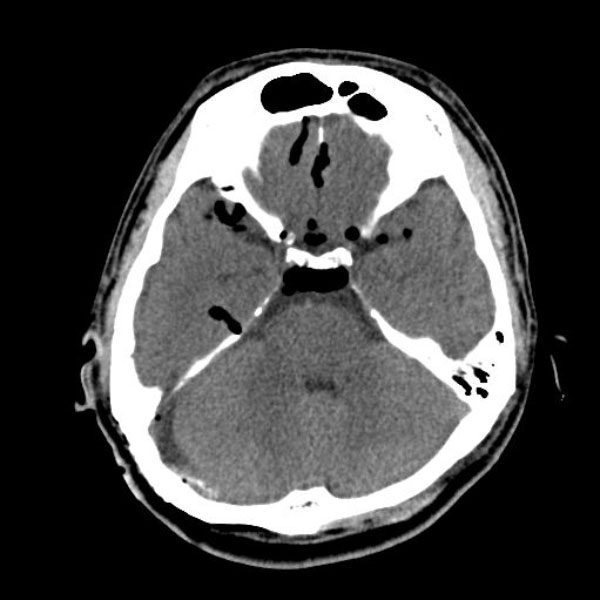

症例 '26年2月

No.

577

大阪府の病院

'26年2月

40代

右顔面痙攣

(痙攣をとること)

手術前

減圧前

減圧後

術後血管撮影